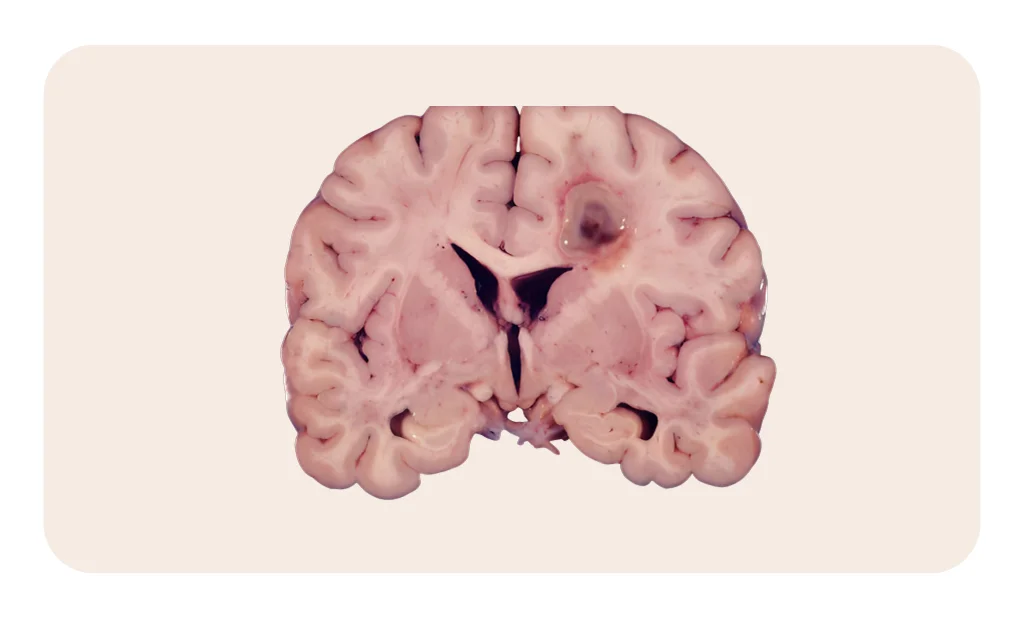

Intraventricular tumours are rare growths that occur within the ventricles—fluid-filled cavities in the brain responsible for producing and circulating cerebrospinal fluid (CSF). These tumours can lead to hydrocephalus (fluid buildup), headaches, vision changes, and neurological deficits due to their deep location.

Intraventricular Tumour